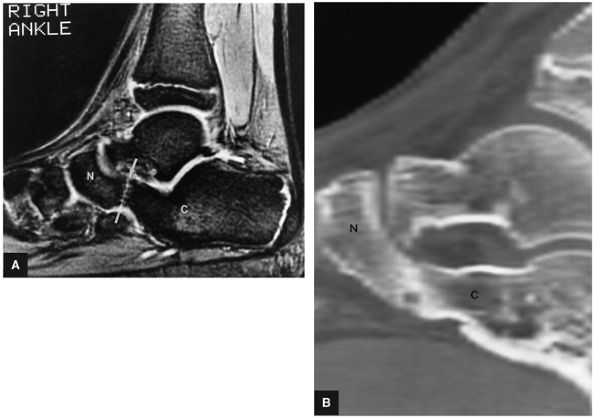

Thickening (Fig. 5.180) or absence of the ligament in acute injury

-

Subacute to chronic residual thickening in a healed and scarred ligament (Fig. 5.181)

Chronic instability associated with attenuated or hypoplastic ligament with sharper, more defined ligament margins